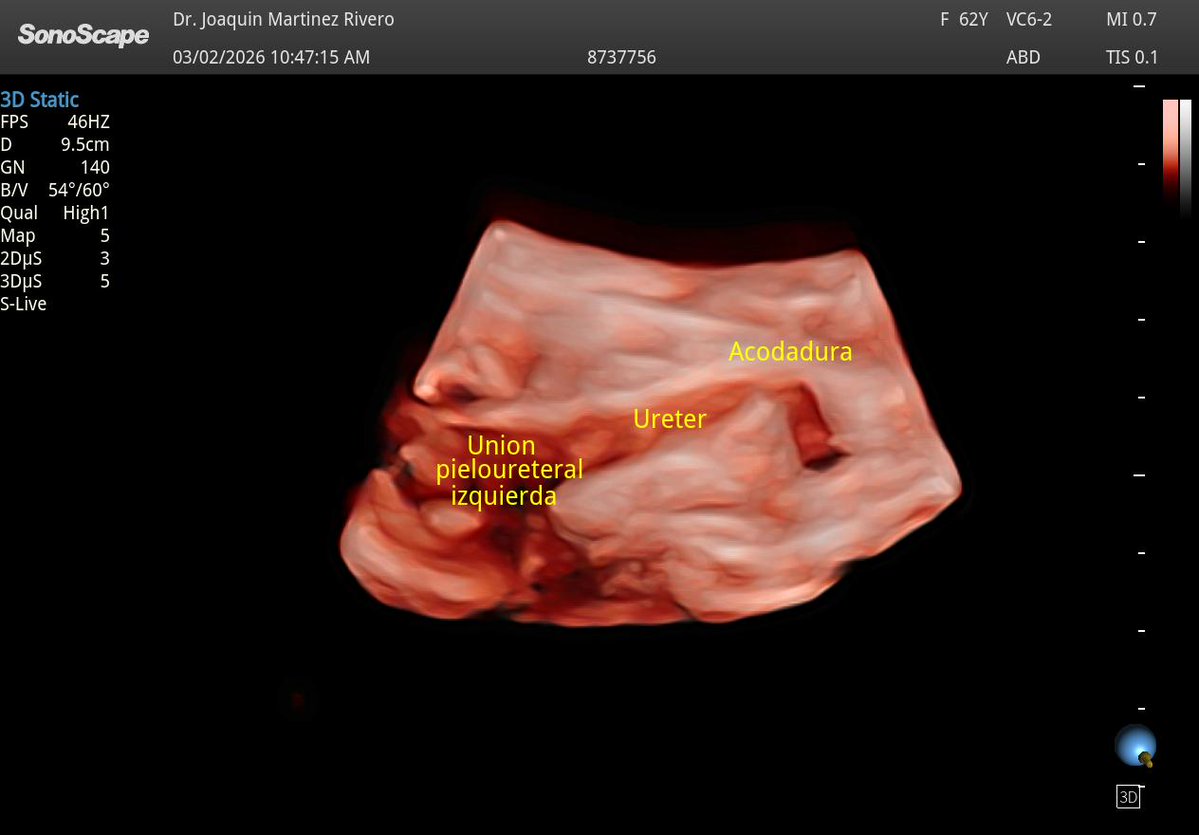

Acodadura ureteral izquierda. Confirmación con CT.

@javiteigell @NephroP @OswaldoRamosN @PierpaDiNick @y_interna @yaletung @SonoSamMD @curromir @zbriote @ABCDEcografia @AlvarezHigueras @ignaciomsb @jpalacinp @EcosemfyC @USPed_Latam @GTEcoPed @GTECOSEMI Sí, acá el 3D le hizo justicia al caso. 🙏🏻🙏🏻🙏🏻🙏🏻🙏🏻

Español

@JMMR83 @NephroP @OswaldoRamosN @PierpaDiNick @y_interna @yaletung @SonoSamMD @curromir @zbriote @ABCDEcografia @AlvarezHigueras @ignaciomsb @jpalacinp @EcosemfyC @USPed_Latam @GTEcoPed @GTECOSEMI Qué bien se ve este!!